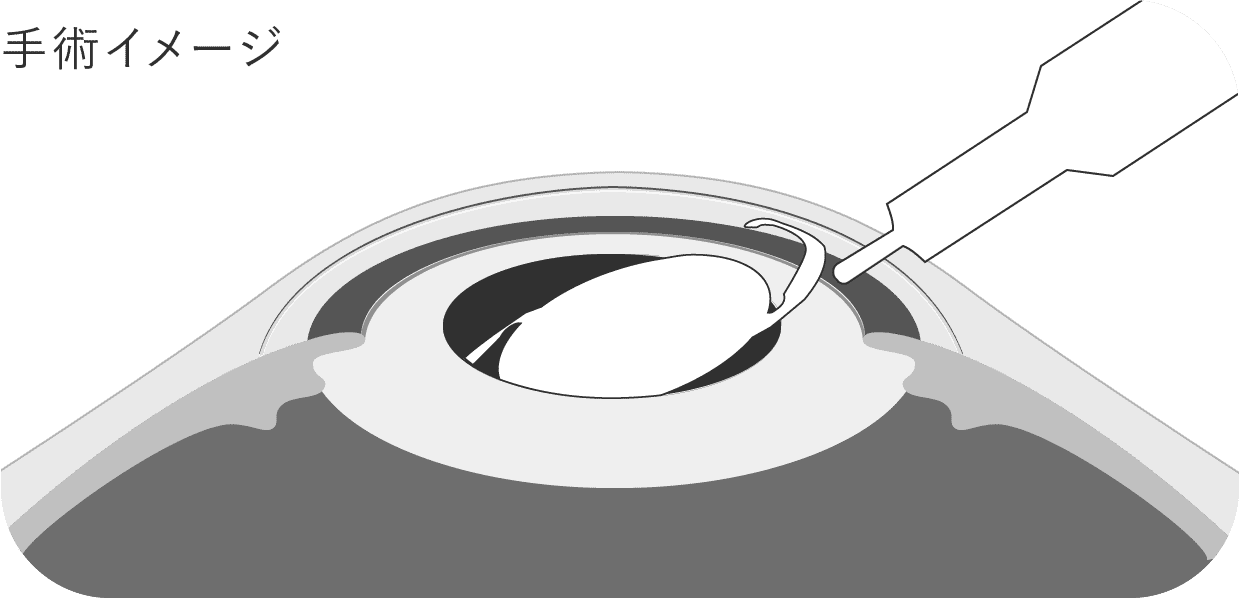

濁った水晶体が元に戻ることはありません。

そのため、手術で水晶体を取り除き、代わりに「眼内レンズ」という人工のレンズを挿入し、見え方を改善します。

手術と聞くと大掛かりに思えるかもしれませんが、技術の進歩により今では多くの医療機関で日帰りで実施されています。

当院の白内障手術も、日帰りにて承っております。

白内障手術の時間は片眼で通常15〜20分です。

- 1切開します。

- 2濁った水晶体を砕いて吸い出します。

- 3眼内レンズを挿入します。